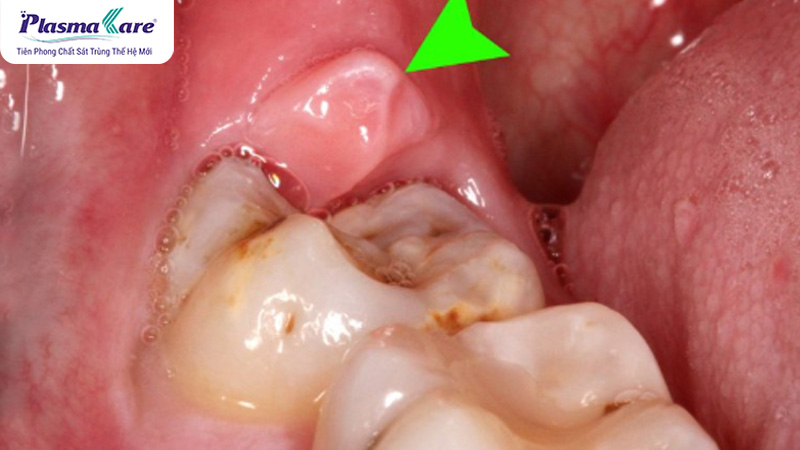

Hình ảnh viêm lợi trùm răng số 8